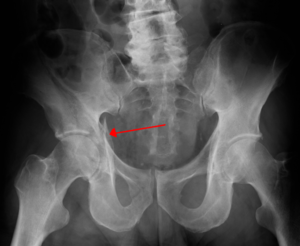

Acetabular pelvic fractures

Radiographically

- Consider obtaining AP, Judet, and inlet/outlet films

- Iliopubic line extends from ilium to superior pubic ramus

- Ilioischial line- extends from ilium to ischial ramus forming radiographic teardrop, "U" shaped, on AP pelvis

- Quadrilateral plate forms medial wall of acetabulum